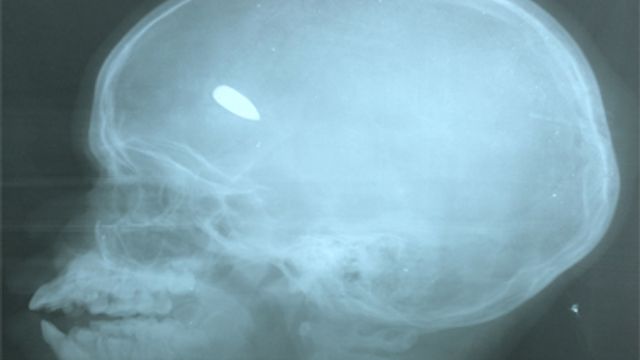

“La morte tra le mie braccia di un bambino soldato. Avrà avuto tra i 15 e i 16 anni. Me lo avevano portato tutto coperto di sangue con una ferita alla testa, ma non ho potuto far nulla per salvarlo. Sono tantissimi i ragazzini arruolati, sia dai ribelli islamici scesi dal nord che dalle milizie cristiane di autodifesa che si combattono nella capitale. Poi ci sono i mercenari e in mezzo i civili”.